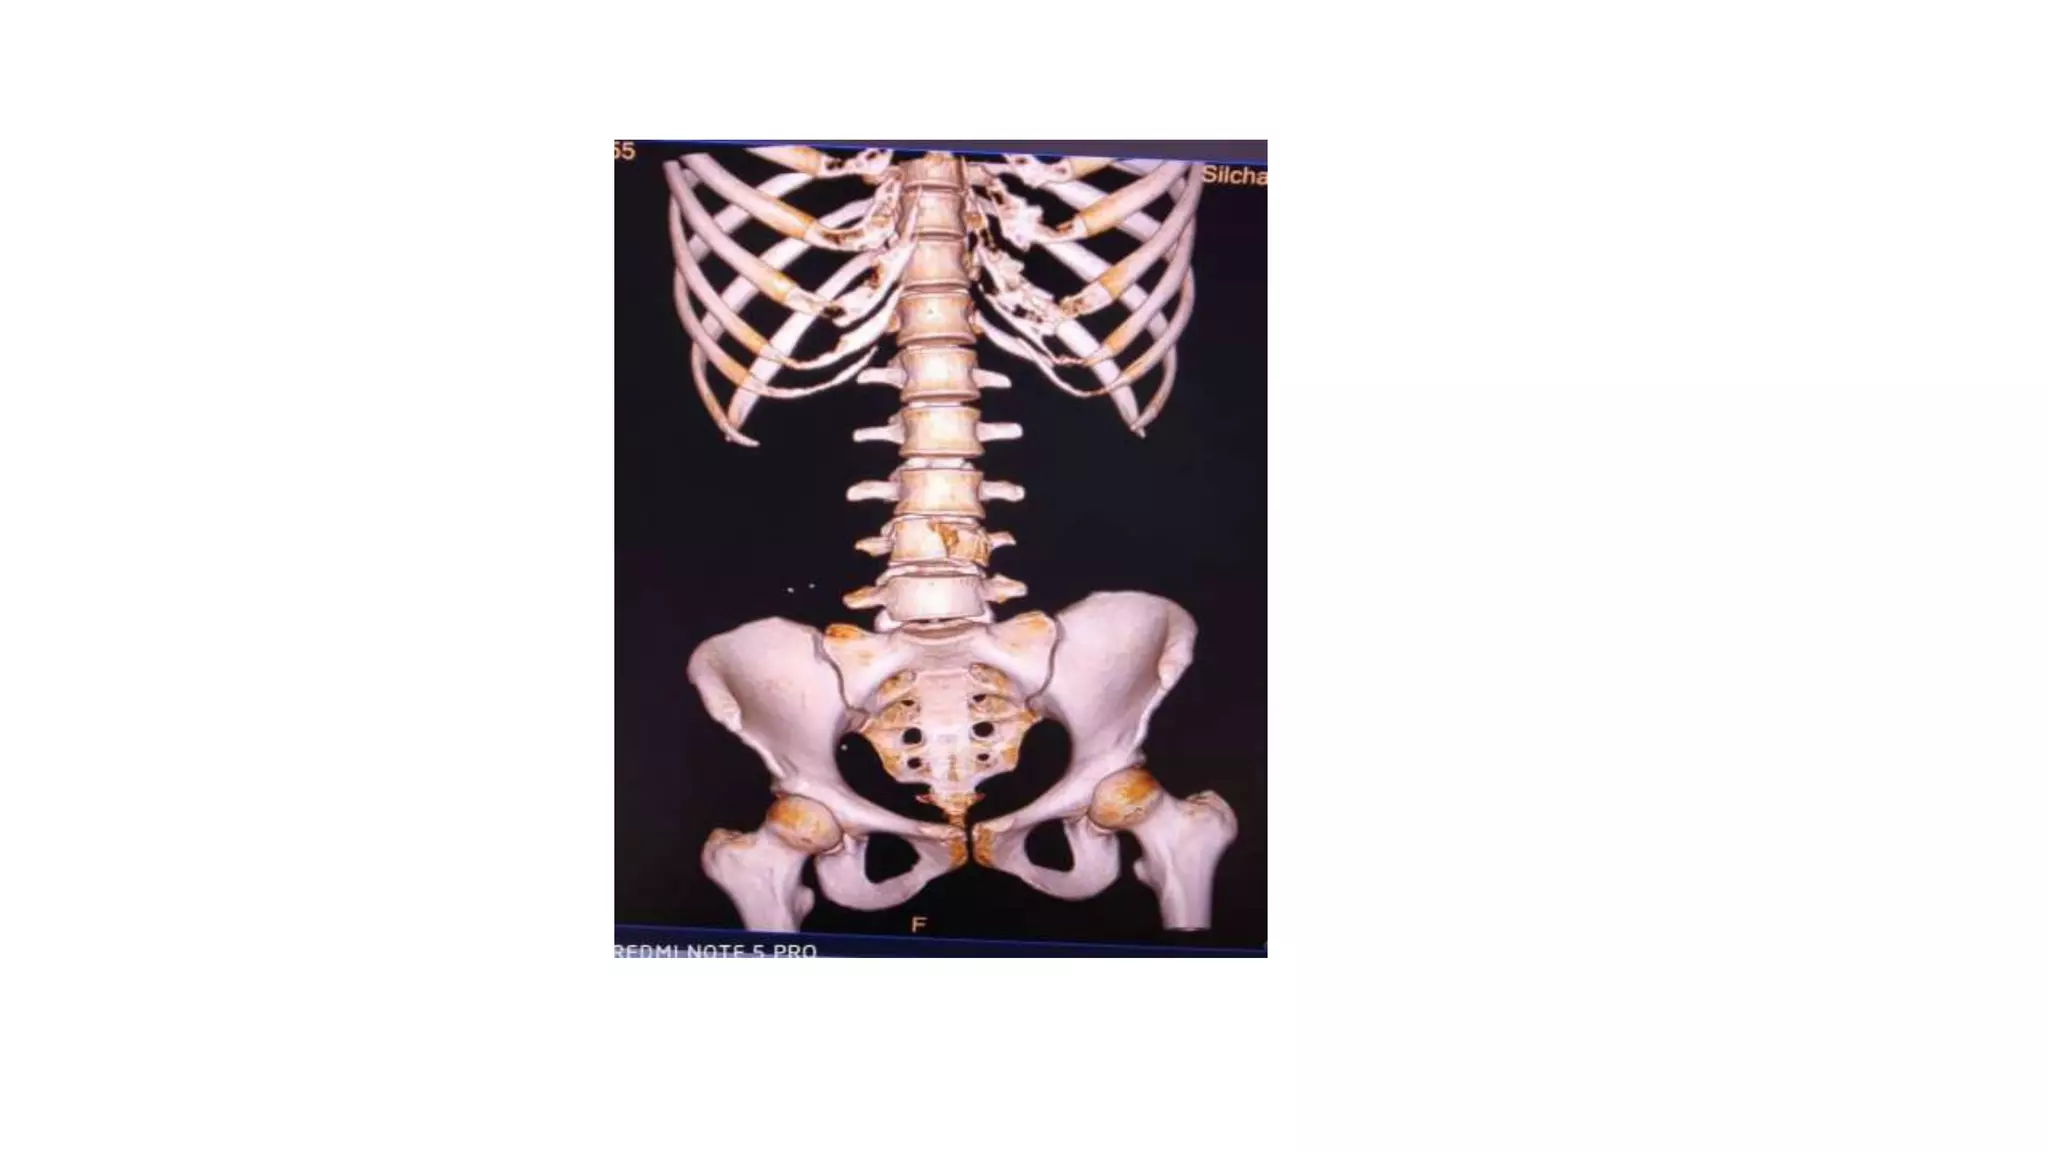

• The multislice volume imaging allows reconstructions in

virtually every plane as well as curved reconstructions in

patients with scoliosis.

• Three-dimensional volumetric reconstructions can be made

to make illustrative images for the clinicians.

ANATOMY OF PELVIS

• The bony pelvis consists of innominate bones, each

with three parts (ilium, ischium and pubis), sacrum

and coccyx.

• It protects the pelvic viscera, provides attachment

for the muscles of the trunk and lower limb, and

enables stable transfer of the body weight from the

spine to the femur.

• The false pelvis is formed mainly by the iliac fossae and

is largely filled by the iliopsoas muscles.

• The true pelvis is bounded posteriorly by the sacrum

and coccyx, laterally by the obturator membranes,

sacrospinous ligaments, and anteriorly by the pubic

bones.

ANATOMY OF PELVIS •The bony pelvis consists of innominate bones, each with three parts (ilium, ischium and pubis), sacrum and coccyx. • It protects the pelvic viscera, provides attachment for the muscles of the trunk and lower limb, and enables stable transfer of the body weight from the spine to the femur. • Its divided into false (major) and true (minior) pelvis, by the ileopectineal line: the smaller inferior part is the true pelvis and the larger superior part is the false pelvis.

• 56.

• The falsepelvis is formed mainly by the iliac fossae and is largely filled by the iliopsoas muscles. • The true pelvis is bounded posteriorly by the sacrum and coccyx, laterally by the obturator membranes, sacrospinous ligaments, and anteriorly by the pubic bones.